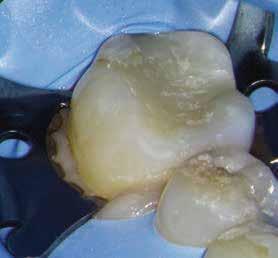

A diagnózisunk reverzibilis pulpitis volt. Periapicalis elváltozás jelenlétét nem vélelmeztük. A fogban lévő amalgámtömés eltávolítása során körülbelül egy 3 mm átmérőjű pulpaseb keletkezett a buccalis pulpaszarvnak megfelelően (1. a–g. ábrák) Mivel nem tapasztaltunk jelentős vérzést, és a diagnózisunk reverzibils pulpitis volt, ezért a direkt pulpasapkázás elvégzése mellett döntöttünk.

A kavitást 2,5%-os nátrium-hipoklorit oldattal fertőtlenítettük, majd sűrű konzisztenciájú kalcium-szilikát alapú anyagot (CeraPutty, Meta Biomed) készítettünk elő a direkt pulpasapkázás elvégzéséhez. Az első kezelés végén röntgenárnyékot nem adó ideiglenes töméssel (NexTemp LC, Meta Biomed) zártuk

az üreget annak érdekében, hogy a direkt pulpasapkázásra használt anyag megfelelő pozícióját radiológiailag ellenőrizni tudjuk. A második ülés során kompozit tömőanyagból (Ezfil, Meta Biomed) direkt adhezív restaurátumot készítettünk.

A kezelést követően a beteg tünetmentes volt. A kérdéses fog a kontrollvizsgálatok során végzett szenzibilitástesztekre fiziológiás reakciókat adott. A hat hónapos kontroll alkalmával készített röntgenfelvételen a sérülésnek megfelelően széles dentinhidat észleltünk (2. ábra). A restaurátum a hároméves kontroll során is megfelelőnek bizonyult (3. ábra)